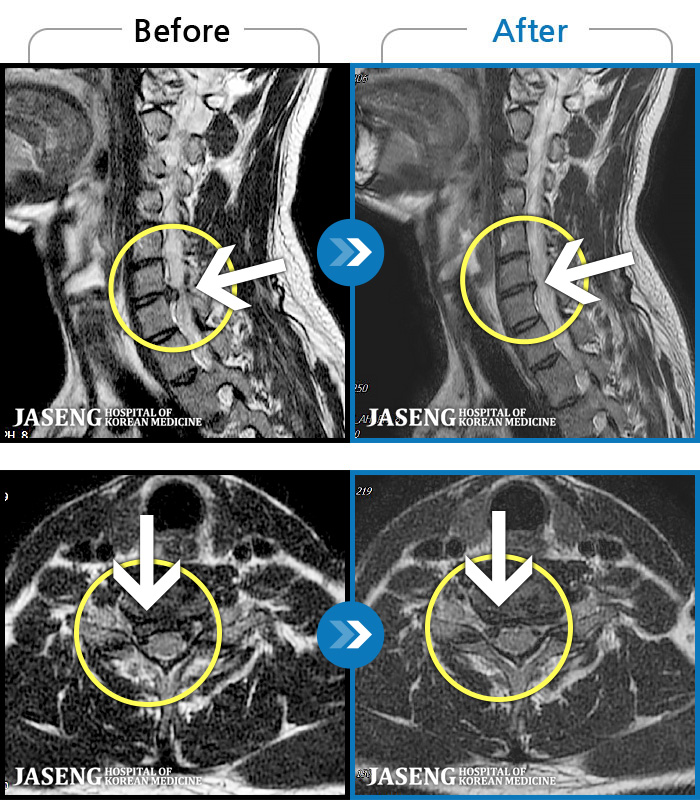

자생 비수술 한방통합치료 후

터진디스크가 흡수된 모습

Before

After

비수술 치료만으로

터진 디스크 흡수

튀어나온 디스크 대비,

터진 디스크 치료 효과 우수

디스크 흘러내린 정도가

심할수록 흡수 가능성 증가

치료 후 장기추적관찰 결과,

환자 90% 이상 치료 만족